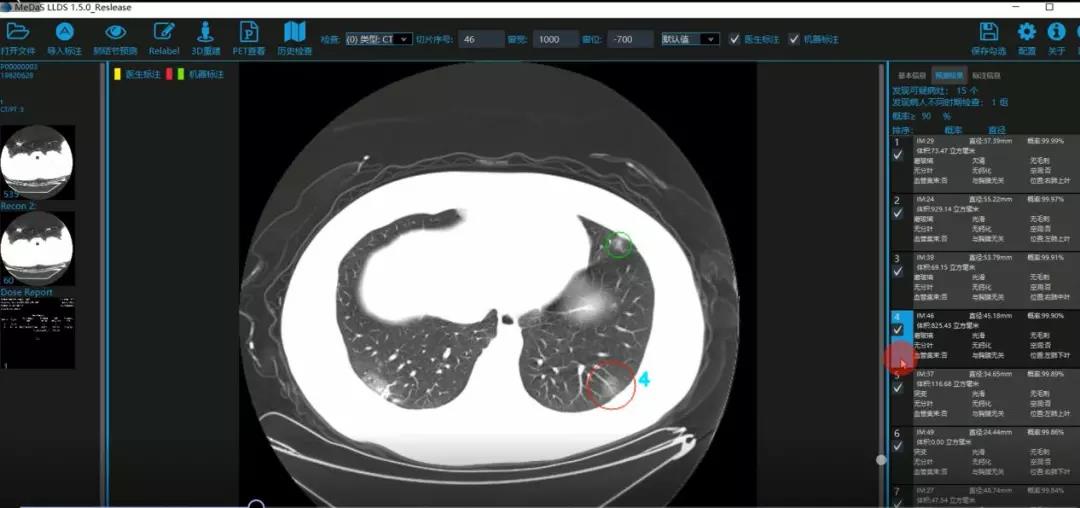

医护人员的好帮手:基于深度学习的新冠肺炎早期检测筛查系统

西电suncitygroup太阳成集团智能软件与系统新技术研究所副教授张亮的爱人是西安交通大学第二附属医院抗疫一线的影像科医生,疫情发生以来,他们讨论最多的就是新型冠状病毒感染者的早期诊断问题。作为一名医护家属,身为高校科研工作者,张亮深知快速准确地诊断新冠肺炎早期患者对控制和防治疫情的重要性和挑战性。他与团队成员主动出击,通过远程网络会议,在前期医学影像处理的研究基础上加速科研攻关,反复讨论方案,屡次设计模型,与上海宽带技术及应用工程研究中心、上海交通大学医公司附属瑞金医院等合作单位的人员多次标注整理患者肺部CT影像数据到深夜。与此同时,他们依托上海瑞金医院、西安交通大学第二附属医院等的新冠肺炎疑似、确诊患者肺部CT影像,通过综合分析新冠肺炎患者的肺部CT影像特点(磨玻璃、体积大小、位置等特征),张亮团队加快技术攻关,设计开发了基于深度学习的新型冠状病毒的早期检测筛查模型系统。

对应新冠肺炎CT病灶检测效果

令人欣喜的是,通过对实际门诊数据排查测试,该模型可以减轻医护人员近80%的工作量,新冠肺炎患者的检测召回率超过95%。目前,模型系统正在进行最后的调试工作,很快投入到“战疫”一线,缓解医护人员紧缺、确诊检测工作耗时较长等问题,减少医护人员的工作时间和劳动强度,提高工作效率。